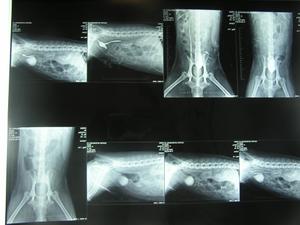

IMPRESIÓN DE LAS IMÁGENES: mediante la impresora láser DRY-VIEW, que está conectada en la network del hospital, imprimimos una o varias imágenes en el mismo soporte. |

SOPORTE:varias radiografías en el mismo soporte plástico |

NEURORADIOGRAFÍA: En neurología es de gran ayuda muchas veces el realizar copias en negativo para la observación de los contrastes mielográficos. |

OTROS FORMATOS DE IMPRESIÓN: |